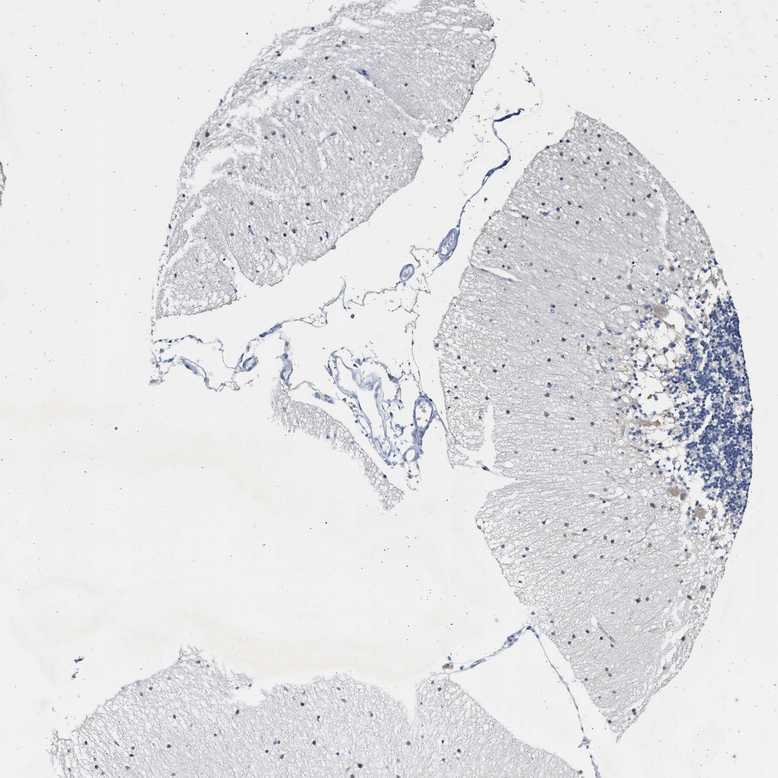

CEREBELLUM - Antibody stainingi

Antibody staining in the annotated cell types in the current human tissue is reported as not detected, low, medium, or high, based on conventional immunohistochemistry profiling in selected tissues. This score is based on the combination of the staining intensity and fraction of stained cells.

Each image is clickable and will lead to virtual microscopy that enables deeper exploration of all samples and also displays staining intensity scores, fraction scores and subcellular localization as well as patient and tissue information for each sample.

Antibody HPA019862

Purkinje cells Low

Cells in granular layer Not detected

Cells in molecular layer Low